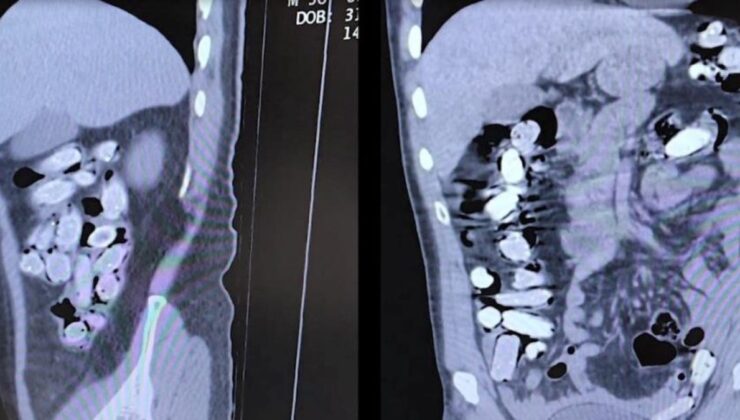

Tatvan Devlet Hastanesine sevk edilen şüphelilerin röntgen ve tomografi görüntülerinde mide ile bağırsaklarında çok sayıda yabancı cisim bulunduğu tespit edildi.

Yapılan tıbbi müdahale ile şüphelilerin paketleyerek yuttuğu toplam 96 adet daralı ağırlığı 1 kilogram 340 gram Afyon sakızına el konuldu.